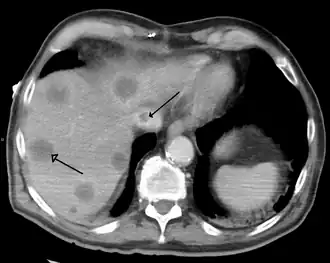

A gross pathology specimen of liver metastases caused by pancreatic cancer

A previously undiagnosed liver disease may become evident first after autopsy. Following are gross pathology images: